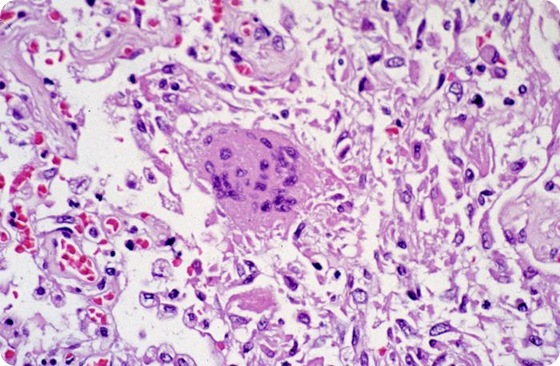

Despite its dramatic entrance into the domain of worldwide public health threats in 2002, little headway has been made therapeutically toward preventing or treating SARS after infection. But GRFT, a lectin protein derived from algae, offers a new possible hope. GRFT is thought to exert its anti-viral effects by altering the shape of the sugar molecules that line the virus' envelope, allowing it to attach to and invade human cells, where it takes over the cells' reproductive machinery to replicate itself. Without that crucial ability, the virus is unable to cause disease. This photomicrograph reveals lung tissue pathology due to SARS.

Researchers treated experimental mice with GRFT or a sham treatment and then inoculated them with the SARS virus. They analyzed the antiviral activity of GRFT and the extent to which the virus was able to invade and replicate in the mice at two, four and 10 days after infection. They found that mice who had not been treated with GRFT showed 20 times more plaque-forming units of virus than treated mice. They also noted that the lungs of untreated infected mice showed extensive necrotizing bronchitis and prominent edema, while mice treated with GRFT showed evidence of significantly less severe lung damage. Additionally, mice treated with GRFT did not experience the drastic weight loss of untreated mice, which lost 35 percent of their body mass.